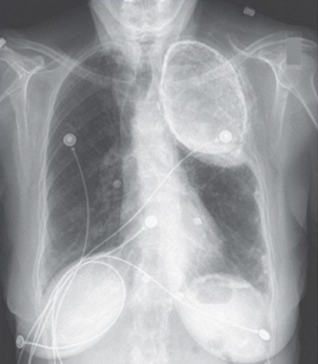

Женщина 86 лет, страдающая гипертонией, обратилась с жалобами на жгучую боль в грудной клетке и эпигастральной области. Из анамнеза - в 1950-х годах проходила лечение по поводу туберкулеза легких. На момент осмотра респираторной симптоматики не наблюдалось. После исключения острого коронарного синдрома было начато лечение по поводу гастроэзофагального рефлюкса, после чего состояние больной улучшилось.Рентгенограмма органов грудной клетки выявила тень высокой интенсивности в верхней части левого легкого. Данную аномалию дифференцировали как застарелую кальцифицированную эмпиему, гемоторакс или олеоторакс.

Учитывая лечение туберкулеза в анамнезе, наиболее вероятным диагнозом стал олеоторакс – способ лечения легочного туберкулеза, который применялся много лет назад и состоял в инстилляции стерильного масла в плевральную полость, в результате чего пораженное легкое сдавливалось. Обычно после лечения, которое могло длиться до 2 лет, масло аспирировали. Как бы то ни было, пациенты, которые не имели жалоб, иногда терялись из виду, и масло оставалось у них в плевральной полости, как и в случае с данной пациенткой.